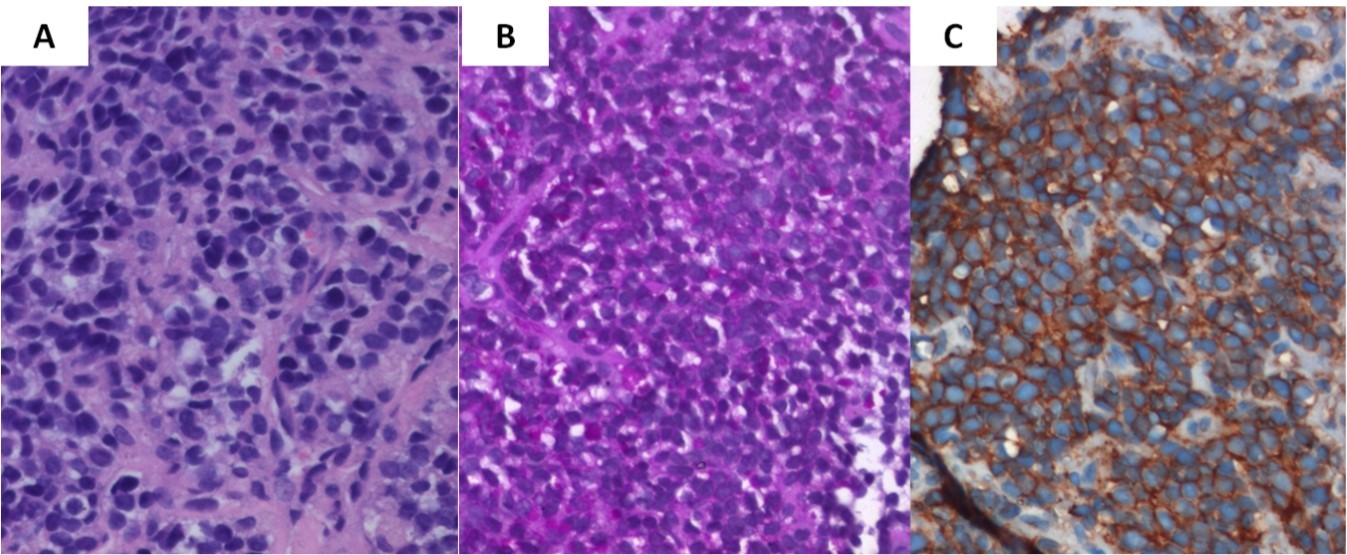

A J-needle biopsy from the extremity tumor showed the tumor to be composed of ‘undifferentiated small blue round cells’ (Figure 3A) with variable cytoplasmic vacuolation. To characterize the lesion further, appropriate special stains and IHC was carried out on the biopsy specimen. The vacuolated cells stained positive for Periodic Acid Schiff (Figure 3B) while the small blue round cells were diffusely membrane positive for CD99 or Mic2 (Figure 3C), focally weak positive for FLI-1, and negative for LCA and desmin suggesting a primary ES/PNET rather than metastases from medulloblastoma. To aid in definitive diagnosis, molecular testing was done showing Ewing’s sarcoma breakpoint region 1 (EWSR1) gene re-arrangement (Figure 4) on fluorescence in-situ hybridization (FISH). Ewing’s sarcoma is strongly associated with translocation t(11;22) in most cases4 and t(7;22) or t(21;22) in some cases, all involving the EWSR1 gene on chromosome 22.

Figure 3.Biopsy from the tibial lesion (A) showed ‘undifferentiated small blue round cells’ on light microscopy (X400, hematoxylin & eosin). Vacuolated cells were positive for Periodic Acid Schiff stain (B), while small blue round cells showed diffuse membrane positivity for Mic-2 (C)